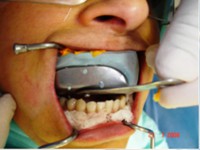

- Coroa protética cerâmica imediata

- Aplicação da cerâmica de baixa fusão direto sobre o pilar